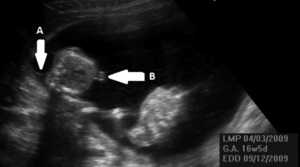

Pierwszym efektem zaburzenia równowagi przepływu krwi między płodami jest zmiana objętości krwi krążącej u obu płodów. Jeden z nich staje się hipowolemiczny i nazywany jest dawcą, a drugi hiperwolemiczny jest biorcą (ryc. 1).

U dawcy hipowolemia powoduje zmniejszenie diurezy, które w badaniu ultrasonograficznym (USG) początkowo objawia się małowodziem, czyli zmniejszeniem się maksymalnej kieszeni płynowej (maximal vertical pocket, MVP) do 2 cm lub mniej. W skrajnej postaci oligurii, czyli anurii, w USG przestaje być widoczny mocz w pęcherzu moczowym płodu, a małowodzie staje się bezwodziem. Zmniejszenie objętości krwi krążącej płód próbuje wyrównać pobieraniem płynu przez łożysko od matki (co w rezultacie daje niedokrwistość i przyspieszenie przepływu skurczowego w tętnicy środkowej mózgu) oraz zwiększeniem oporu obwodowego, czyli wzrostem wskaźników oporu i pulsacji w tętnicy pępowinowej. Skrajna hipowolemia i niedokrwistość prowadzą do niedotlenienia płodu ujawniającego się obrzękiem uogólnionym, a w ostateczności do jego zgonu.5-7

Mechanizmy kompensacyjne uruchamiane przez biorcę w celu wyrównania nadmiernej objętości krwi krążącej początkowo ograniczają się do poliurii i zwiększania się objętości płynu owodniowego. Górna granica normy MVP jest określona przez wszystkich autorów jako 8 cm, jeśli wiek ciążowy nie przekracza 20 tygodni. Natomiast w ciąży starszej niektórzy autorzy zalecają utrzymanie tej granicy na poziomie 8 cm, inni natomiast sugerują jej przesunięcie do 10 cm.5-7